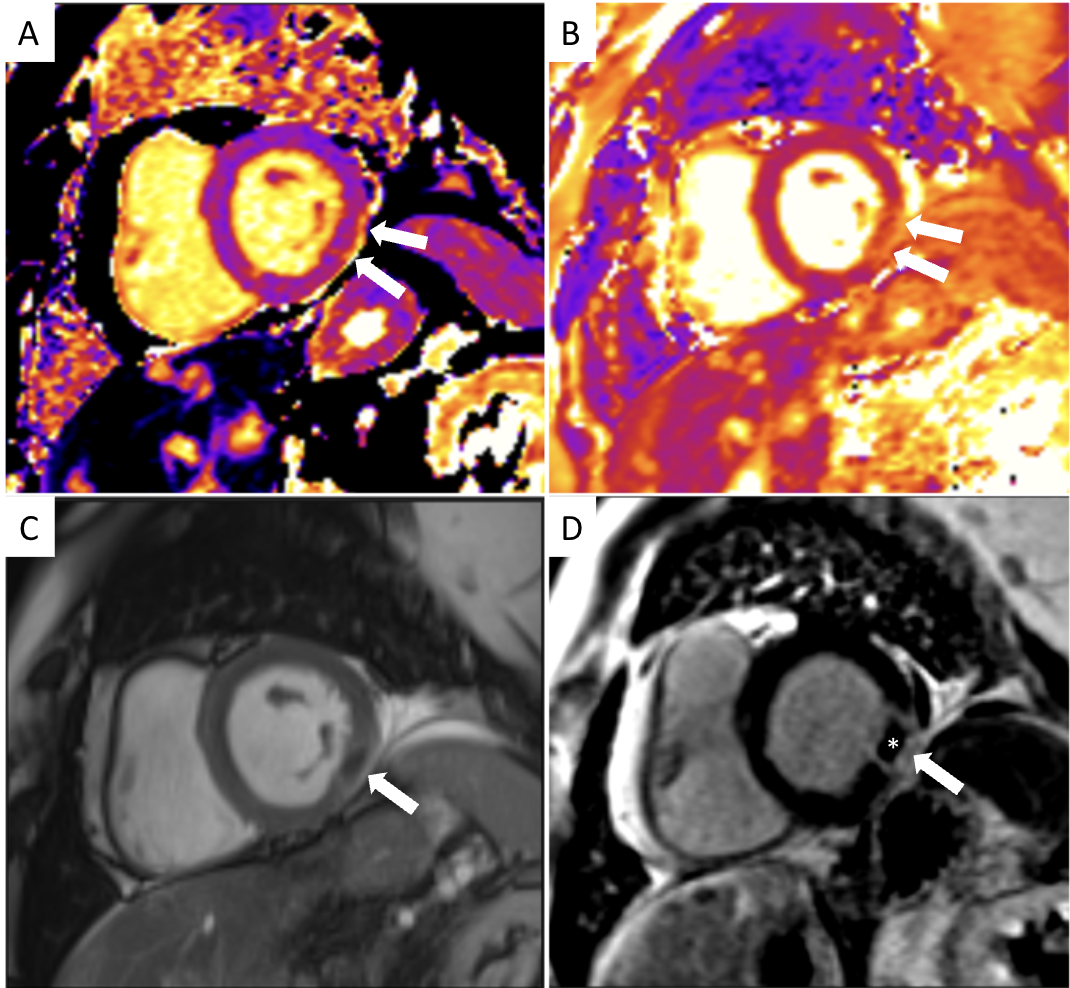

Diagnostic Techniques and Their Most Important Findings: Cardiac MRI performed using a 1.5T magnet revealed mild hypokinesis of the basal lateral wall, with corresponding focal elevation in native T1 and T2 times and transmural late gadolinium enhancement, associated with signs of microvascular obstruction (MVO). Findings were consistent with an acute myocardial infarction (Figure 1) of the basal lateral wall. Subsequent conventional coronary angiography confirmed the absence of obstructive coronary artery disease or coronary emboli. However, physiologic study demonstrated significantly reduced coronary flow reserve (CFR) at 1.6, suggesting microvascular disease. A provocative test with intracoronary acetylcholine demonstrated significant spasm of the left anterior descending coronary artery (Figure 2) accompanied by chest pain and ischemic ST changes on the ECG, confirming diagnosis of vasospastic angina.

Figure 2: Conventional coronary angiography of a 68-year-old female patient before (A) and during (B) intracoronary acetylcholine provocation test. At the 100-mcg dose (B), the patient developed chest pain, ischemic ST changes on the ECG, and angiographic evidence of significant diffuse mid-to-distal LAD vasospasm (arrows in B).

Figure 2: Conventional coronary angiography of a 68-year-old female patient before (A) and during (B) intracoronary acetylcholine provocation test. At the 100-mcg dose (B), the patient developed chest pain, ischemic ST changes on the ECG, and angiographic evidence of significant diffuse mid-to-distal LAD vasospasm (arrows in B).